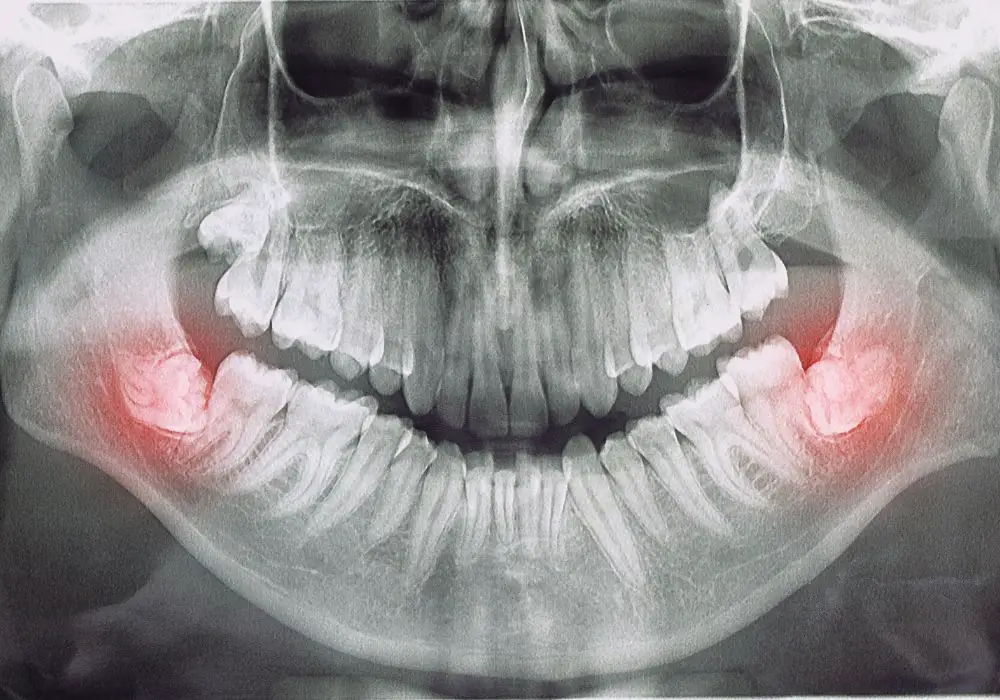

If you have recently undergone wisdom teeth removal surgery, your dentist may have used stitches to close the gum tissue flap after the extraction. Wisdom teeth stitches are necessary to promote healing and prevent bleeding. In this section, we will discuss what wisdom teeth stitches are, how they work, and what to expect during the healing process.